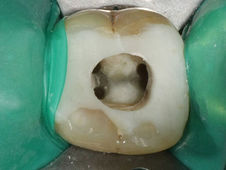

- Für bessere Übersicht und Schutz vor Kontaminierung mit Bakterien wird nach Möglichkeit ein Kofferdam (Spanngummi) gelegt.

Was ist ein Kofferdam?

Bei einem Kofferdam handelt es sich um ein Gummituch mit einem kleinen Loch, welches über den zu reparierenden Zahn gestülpt wird. Durch dieses Spanngummi wird eine bessere Trockenlegung und Übersicht über das Arbeitsfeld erreicht. Er verhindert, daß Bruchstücke von Füllungen (Amalgam) in den Mund gelangen könnten und schützt Sie vor dem unangenehmen Geschmack verwendeter Materialen. Vor allem bei der Wurzelkanalbehandlung wird eine erneute Infektion des Zahnes durch Bakterien im Speichel verhindert und eine bessere Sicht für den Behandlererzielt.